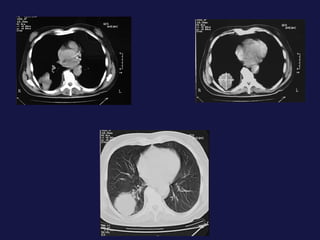

Metástasis al pulmón. El pulmón y el hígado son los mas FREC. Pueden tener varios tamaños. Imágenes nodulares, únicas o múltiples. Pueden cavitarse y calcificación.

Metástasis al pulmón.El pulmón y el hígado son los mas FREC. Pueden tener varios tamaños. Imágenes nodulares, únicas o múltiples. Pueden cavitarse y calcificación.